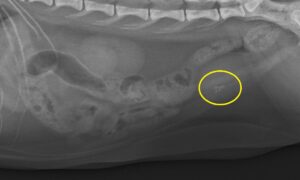

1年前、結石は見られず